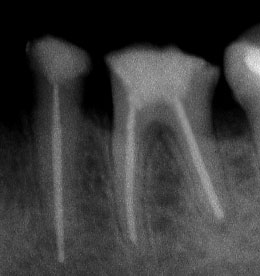

При наличие на огнище на възпаление около корените на зъба добре проведеното лечение води до изчезване на изменението. На снимката долу едва една седмица след пролекуване на каналите се наблюдава известна редукция на патологичния процес. За период от 6 месеца до 2 години е възможно да се наблюдава пълен оздравителен процес.

Понякога е налице патологичен процес около апекса на зъба, който налага да се проведе допълнителна хирургична намеса с цел отстраняване на лезията.